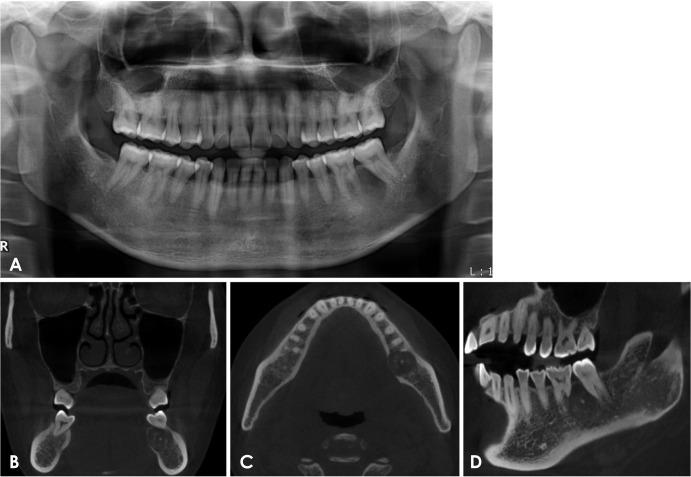

Ossifying fibroma is a slow-growing benign neoplasm that occurs most often in the jaws, especially the mandible. The tumor is composed of bone that develops within fibrous connective tissue. Some ossifying fibromas consist of cementum-like calcifications, while others contain only bony material; however, a mixture of these calcification types is commonly seen in a single lesion. Of the craniofacial bones, the mandible is the most commonly involved site, with the lesion typically inferior to the premolars and molars. Ossifying fibroma of the jaw shows a female predominance. Some reports of ossifying fibroma have been published in the literature; however, this report continues the research on this topic by detailing 3 types of ossifying fibroma findings on panoramic radiographs and cone-beam computed tomographic images of 4 patients. The radiographs of the presented cases could help clinicians understand the variations in the radiographic appearance of this lesion.

骨化性纤维瘤是一种生长缓慢的良性肿瘤,最常发生于颌骨,尤其是下颌骨。该肿瘤由在纤维结缔组织内形成的骨组织构成。一些骨化性纤维瘤由类牙骨质钙化组成,而另一些仅含有骨质材料;然而,在单个病变中通常可见这些钙化类型的混合。在颅面骨中,下颌骨是最常受累的部位,病变通常位于前磨牙和磨牙下方。颌骨骨化性纤维瘤以女性居多。文献中已发表了一些关于骨化性纤维瘤的报告;然而,本报告通过详细描述4例患者全景X线片和锥形束计算机断层扫描图像上的3种骨化性纤维瘤表现,继续对该主题进行研究。所呈现病例的X线片有助于临床医生了解该病变X线表现的差异。